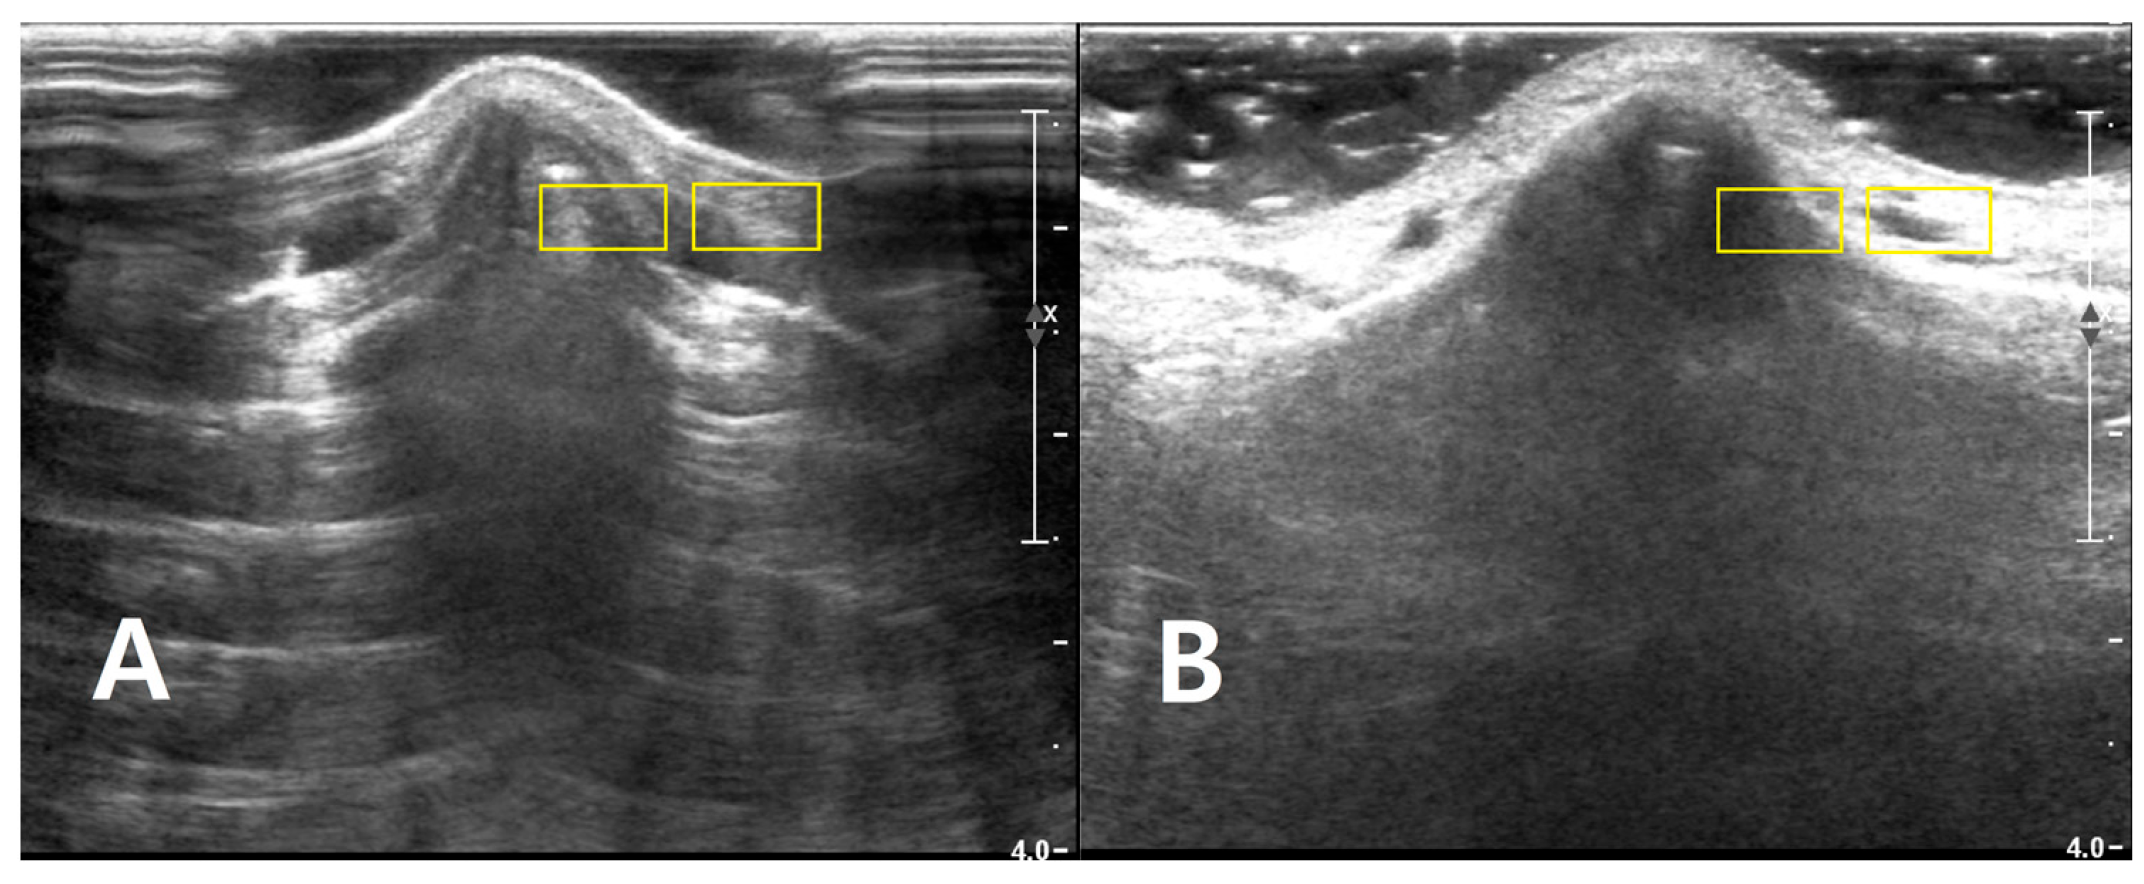

Two rectangular ROIs were defined at a fixed depth and orientation on the PAD image and then reapplied to the LGB image with only minor adjustments to maintain alignment: Cortical ROI (ROI_bone): A small rectangle (approximately 6 × 3 mm) confined to the bright cortical band at the nasal dorsum, avoiding saturated pixels (intensity = 255) and excluding overlying reverberation or shadowing. Adjacent soft-tissue ROI (ROI_soft): A rectangle of similar size placed 1–2 mm lateral to the cortical ROI at the same depth, sampling homogeneous soft tissue (Figure 2). The exact lateral position of the ROIs was adjusted so that, in both PAD and LGB images, ROI_bone and ROI_soft remained aligned to the same anatomical level (depth mismatch ≤ 0.5 mm; angular mismatch ≤ 5°). For subjects with cine data, the same ROIs were propagated across five consecutive frames: the frame with the highest mean intensity within ROI_bone and its two preceding and two subsequent frames. For each frame, the mean (μ) and standard deviation (σ) of the 8-bit gray-level values were recorded for ROI_bone and ROI_soft. For subjects with only static images available, ROI_bone and ROI_soft were repositioned across three to five adjacent locations along the same cortical segment, and measurements were averaged (Figure 3).

Figure 3. Representative sonograms of isolated nasal bone fractures demonstrating ROI placement under two coupling conditions. For two different patients, longitudinal B-mode images of the nasal dorsum are shown with (A) PAD and (B) LGB. Two rectangular ROIs (approximately 6 × 3 mm; yellow boxes) were positioned at a matched depth in each image. One ROI was placed along the hyperechoic nasal cortical line, with care taken to avoid saturated pixels and obvious artifacts. A second, adjacent ROI was positioned 1–2 mm lateral at the same depth to sample homogeneous soft tissue. These examples illustrate the standardized ROI placement used across PAD and LGB images for subsequent CNR and SNR analyses. All images were acquired using the ultrasound presets described in Section 2.4 (depth, 4.0 cm; single focal zone at the nasal cortical interface). The images were cropped by 2.0 cm in the vertical direction to exclude the non-informative anechoic coupling medium visible on the screen; no additional rescaling was performed.